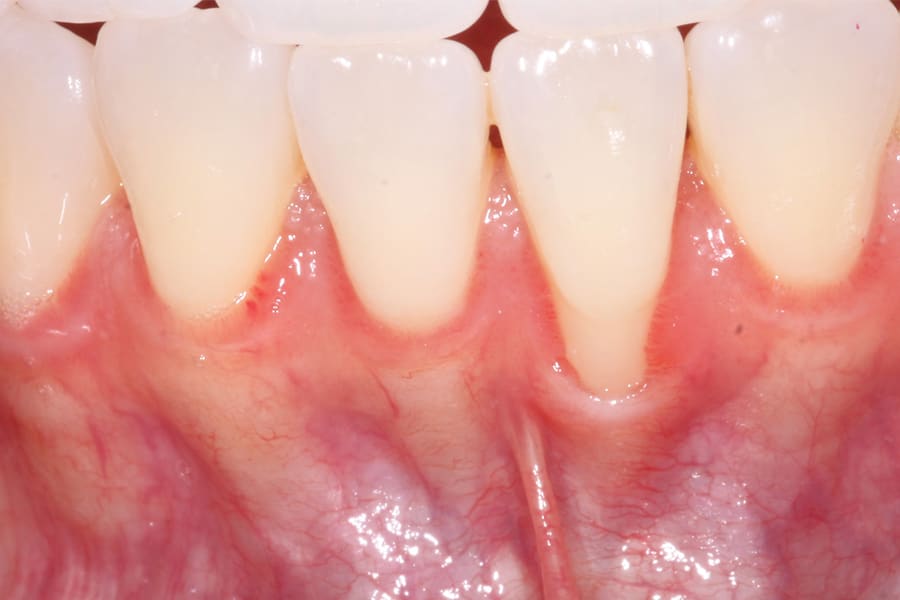

There are, however, some unfavorable long-term ramifications of this design. Due to the nature of stainless steel, which has memory and over time will partially return to its original shape, these twisted lingual retainers may "unwind" or uncoil and exert unintended forces on the teeth to which they are bonded (Figure 5 and Figure 6, Figure 8 through Figure 11, Figure 14 through Figure 16). This leads to excessive labial or lingual root torquing movements, often resulting in highly undesirable recessions, dehiscences, and fenestrations. Because it may take years for this occurrence to manifest, the orthodontist (who usually places the retainer) is typically both unaware of the situation, as he or she does not customarily follow patients for such long-term periods, and free of blame. The periodontal implications of this outcome can be highly detrimental, as seen in the cases presented herein.

Although spontaneous improvement of the investing tissues is often observed through orthodontic correction (Figure 7 and Figure 13),5 additional corrective action is frequently indicated afterwards, particularly when cosmetics are to be considered. A recession defect case is depicted in Figure 17 through Figure 26 in which corrective action was necessary and accomplished through aligner therapy followed by connective tissue grafting.6 It should be noted that although this corrective scheme may successfully achieve an acceptable cosmetic and functional result, it is not likely a regenerative outcome in the sense that a previously dehisced root surface typically will not attain ligamentous insertion into freshly laid cementum. A long junctional epithelium or connective tissue attachment at best is the more likely outcome. Consequently, a preventive approach initially would be more desirable.